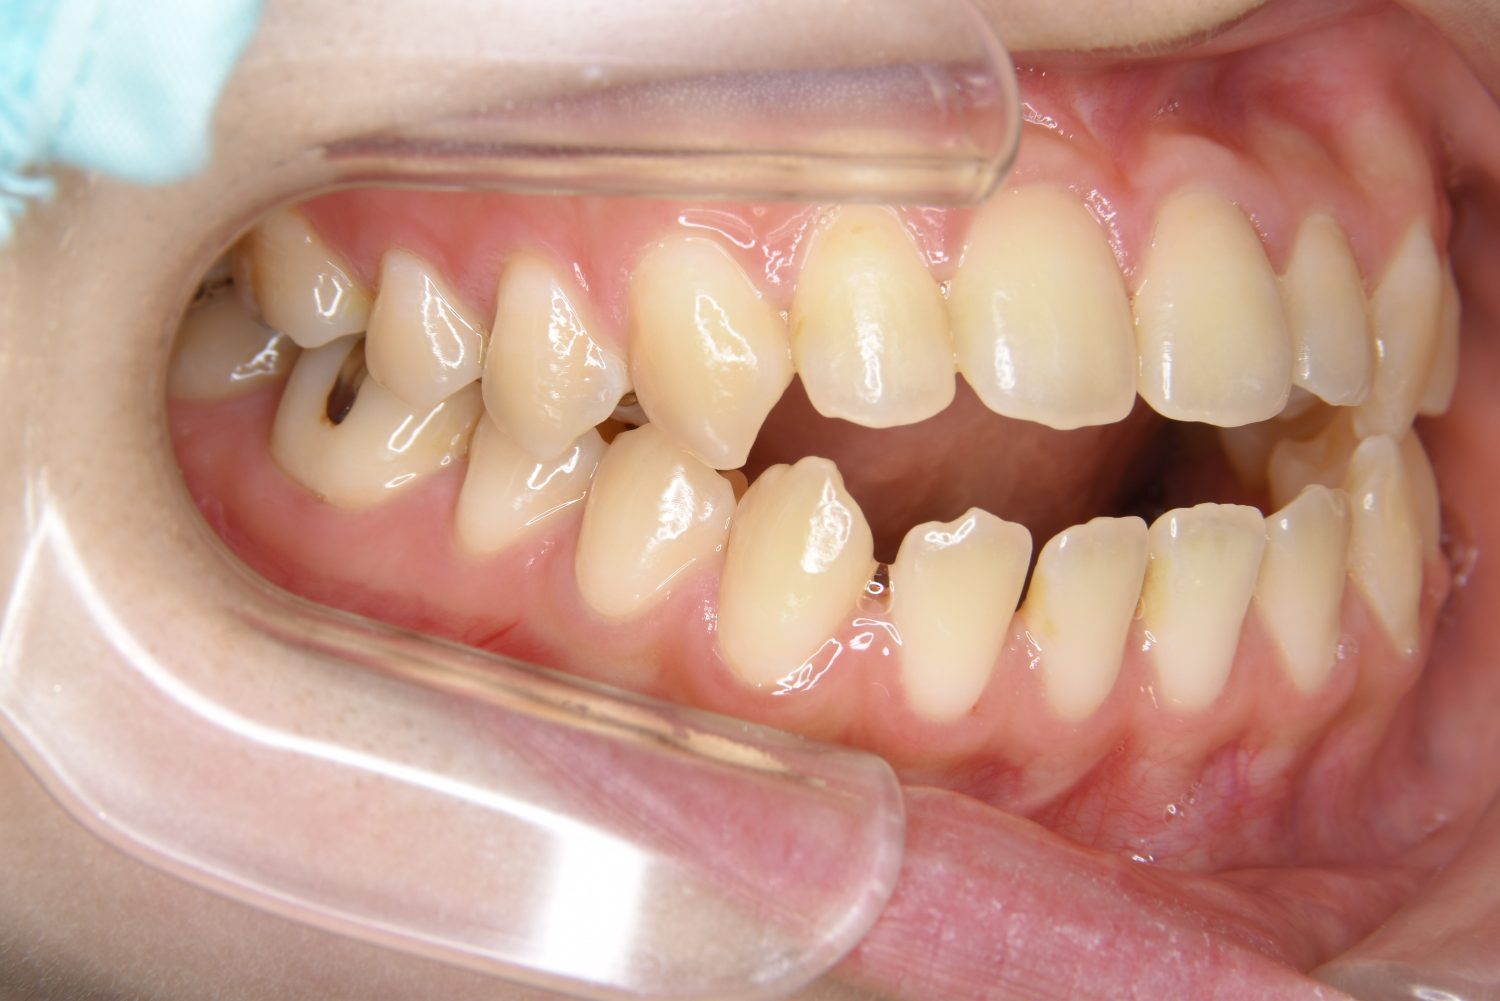

叢生の症例紹介①

Before

主訴

前歯のガタガタが気になる。

治療内容

上顎左側第一小臼歯を抜歯し、アライナー(インビザライン)にて治療を行いました。

左上の側切歯が完全に内側に入り込んでいる状態でした。左上の第一小臼歯のみ抜歯を行い治療を行うことで機能面および審美面を改善しました。